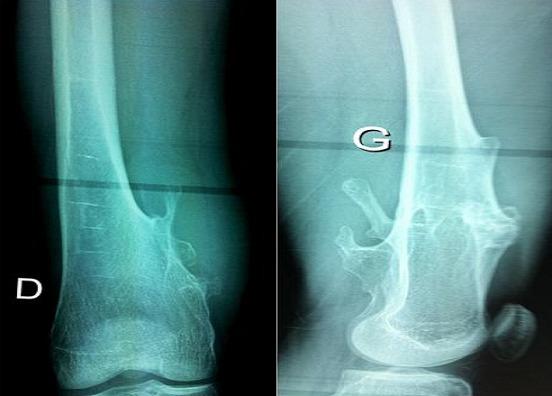

Vascular complications from osteochondroma are rare and include essentially stenosis, occlusion, and pseudoaneurysms. The authors report an original case of intraoperative rupture of undiagnosed popliteal artery pseudoaneurysm during resection surgery for a distal femur osteochondroma.

骨软骨瘤引起的血管并发症很少见,主要包括狭窄、闭塞和假性动脉瘤。作者报告了一例在股骨远端骨软骨瘤切除手术中,未被诊断出的腘动脉假性动脉瘤术中破裂的罕见病例。